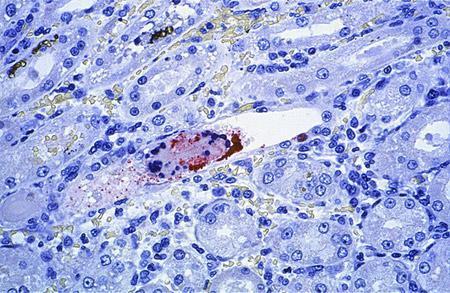

Mikroba karşı erken tedavi hastalardaki ateşi ve hastalığın şiddetini kısmen azaltıyor ancak ölümleri engelleyemiyor.

Nipah virüsü ateş, baş ağrısı, boğaz ağrısı ve kaslarda ağrı gibi belirtilerle kendini gösteriyor, gribe benziyor.

İlerleyen safhada ise belirtiler baş dönmesi, yorgunluk, bilinç değişikliklerine dönüşebiliyor.